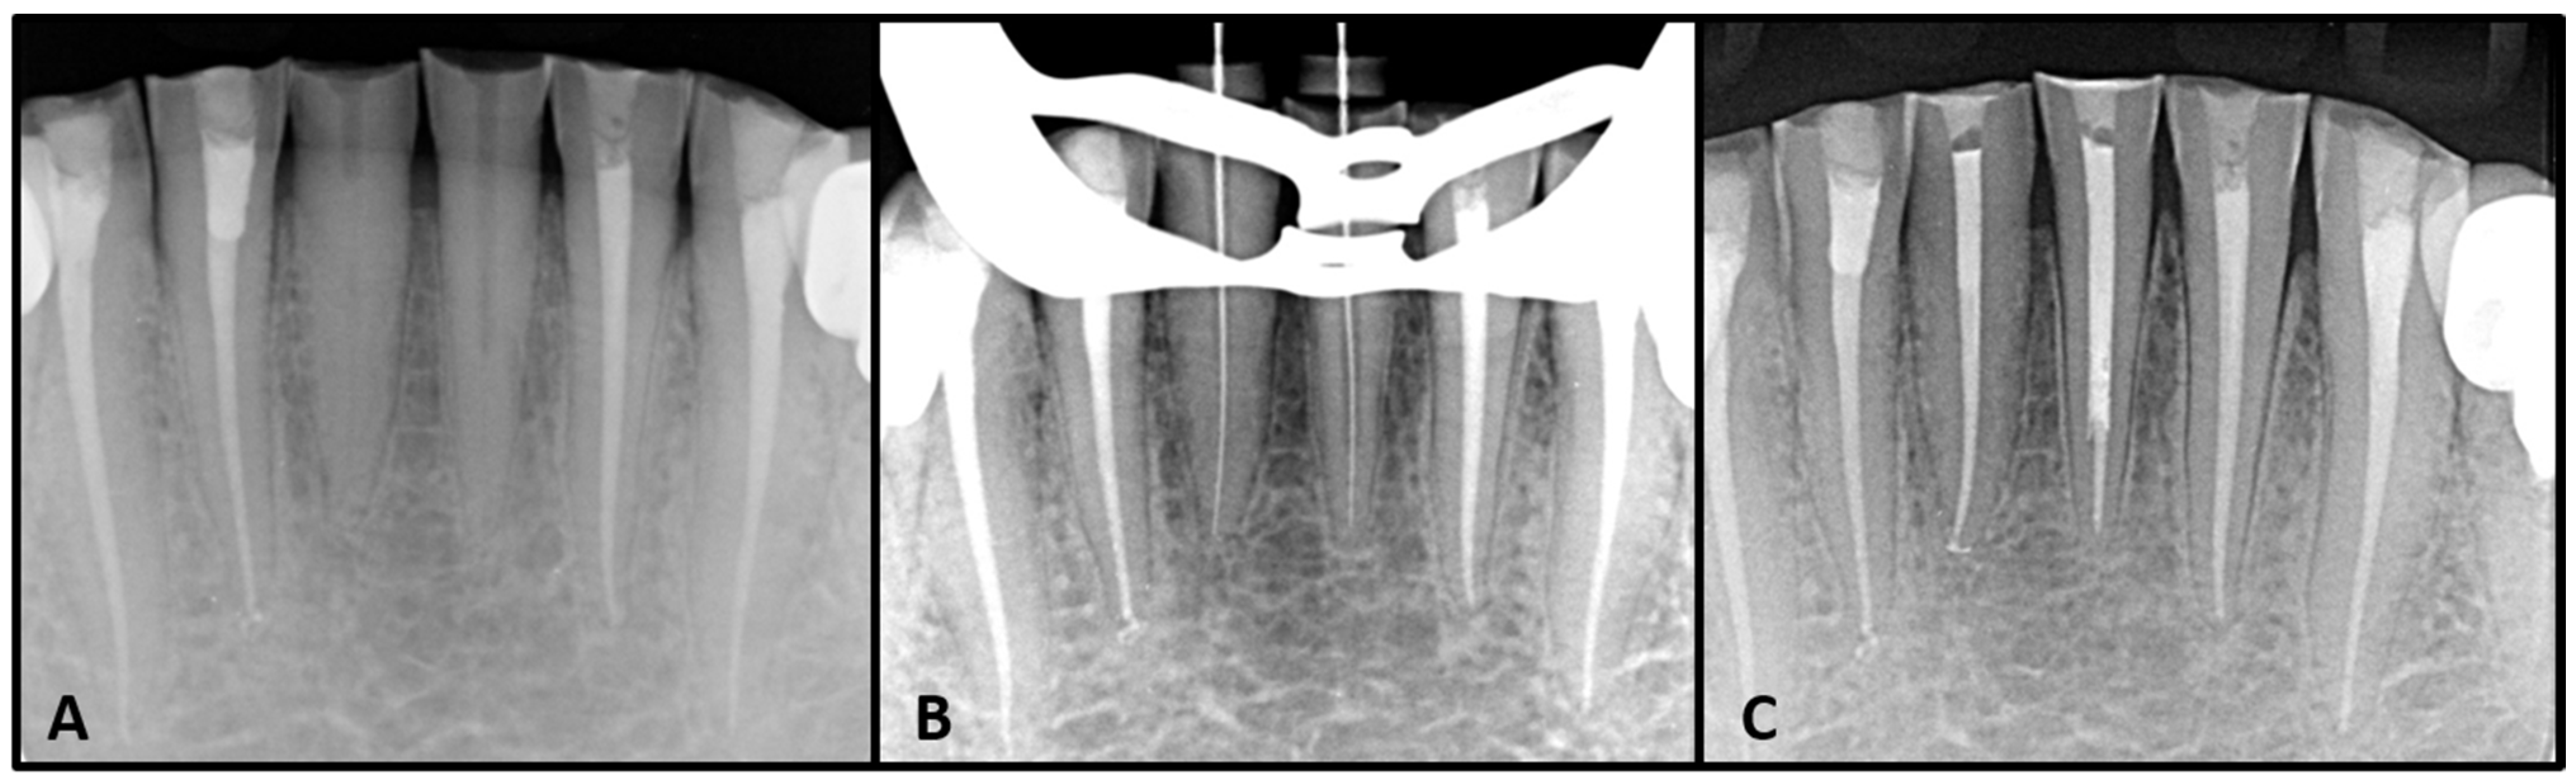

2. Case Report